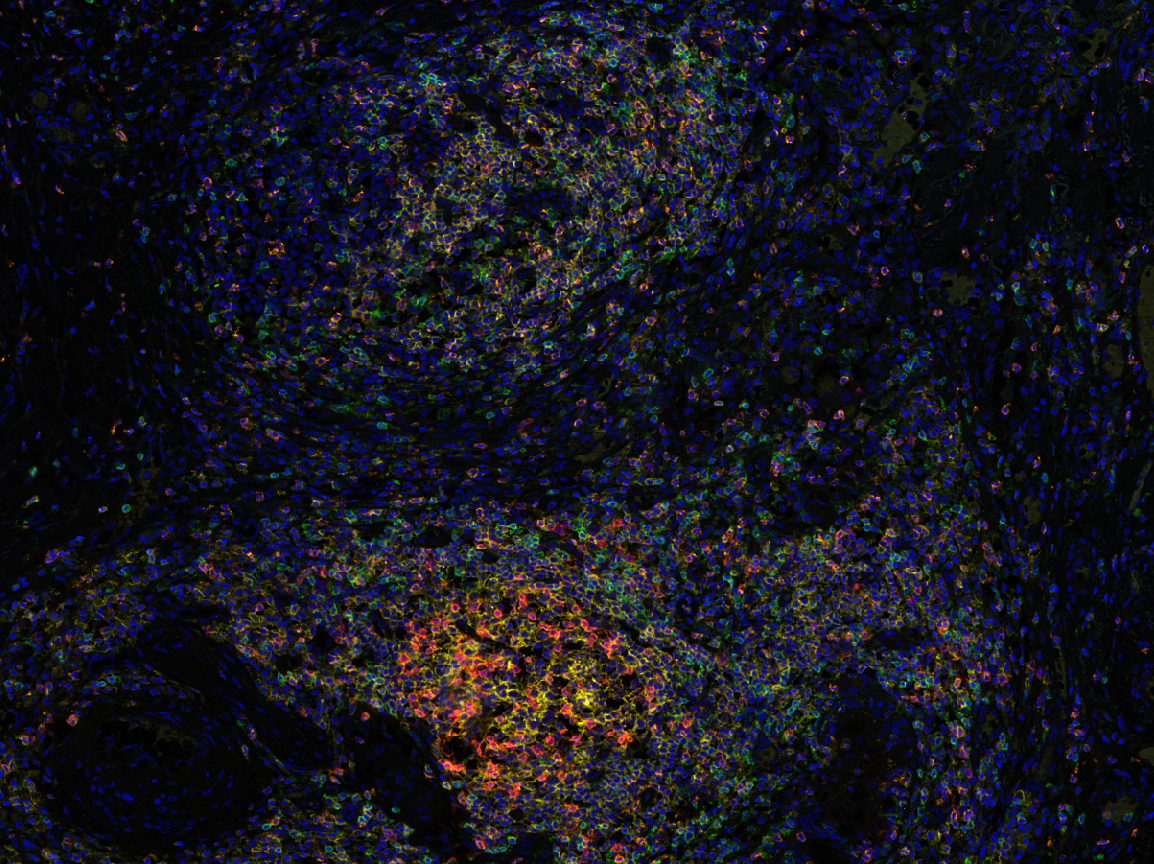

针对两个特殊的蛋白,研究团队运用了多重荧光免疫组化技术进行染色,无论是对小鼠肝脏进行检测还是夹层胶原“三明治”法短期体外培养的原代肝细胞,荧光结果都显示了Sema7aR145W纯合子突变小鼠比野生小鼠组织细胞中的Bsep和Mrp2含量低(图3)。

新闻图片3